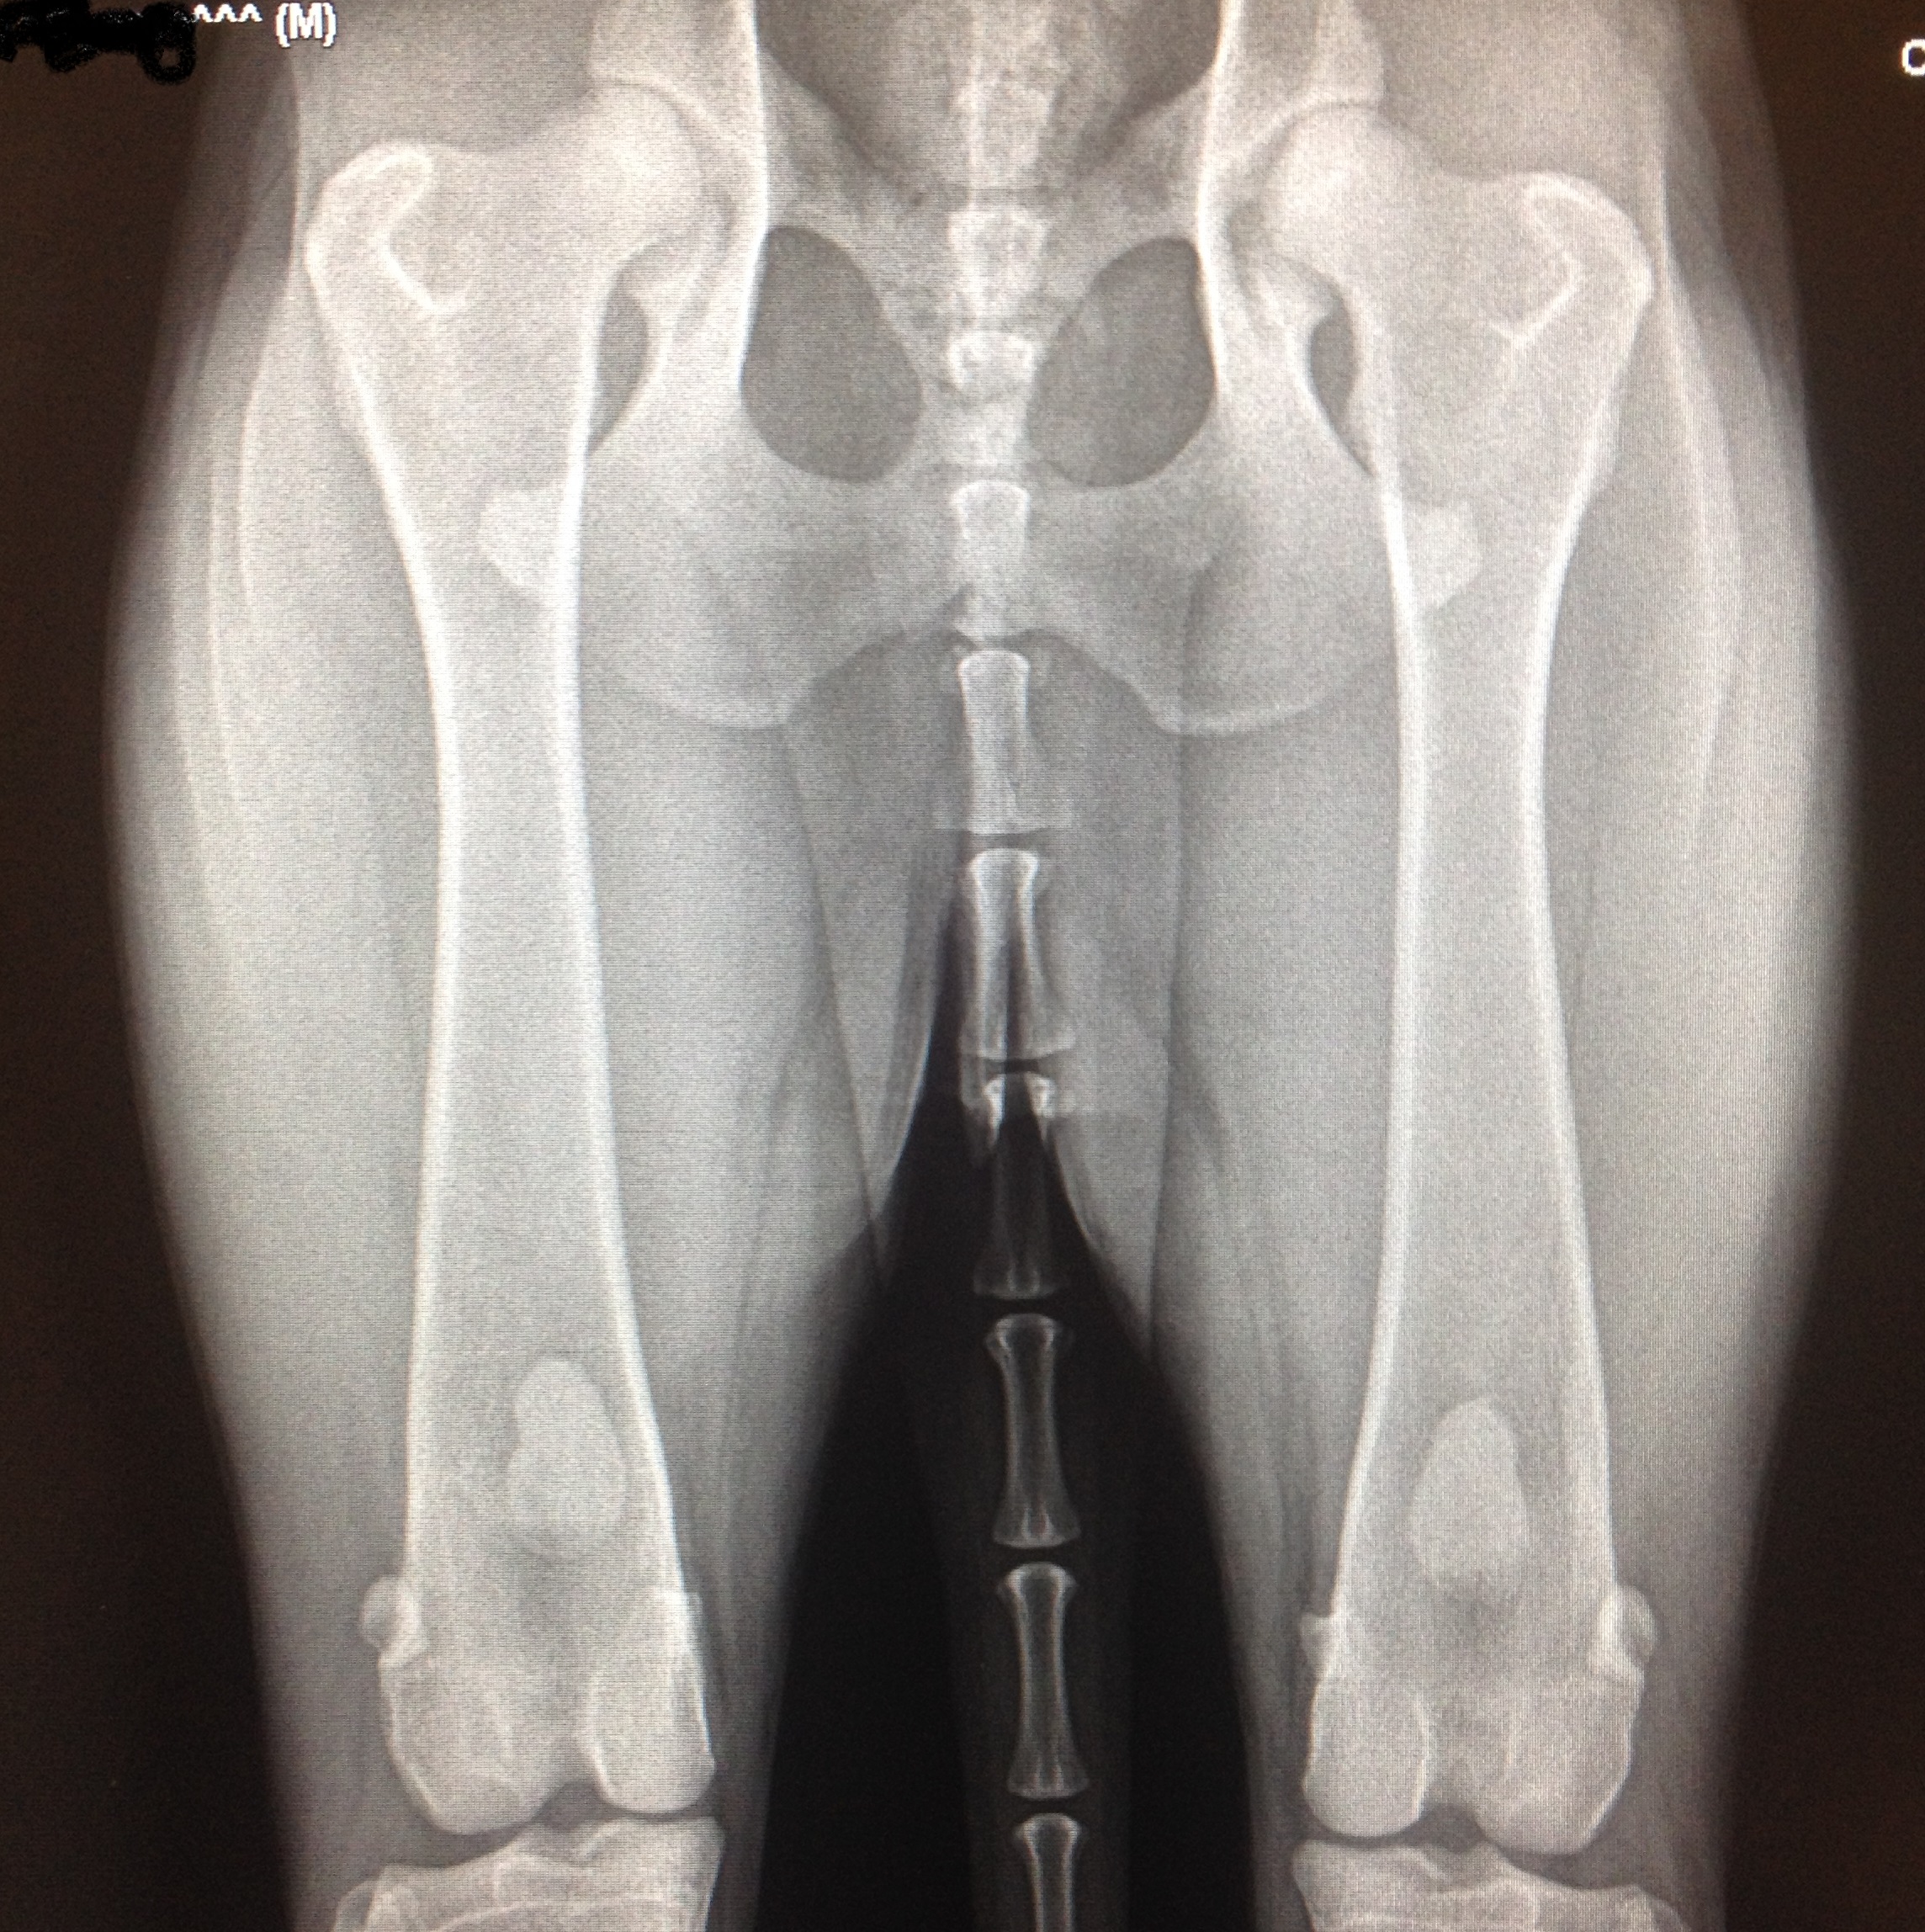

Voici ici des hanches normales. Les têtes fémorales sont bien rondes et entrées profondément dans l’articulation. L’espace articulaire est bien égal indiquant une bonne congruence. Les rebords osseux sont lisses, indiquant l’absence d’ostéoarthrose.

Les deux radiographies montrent des hanches avec une laxité articulaire. Ce sont les premiers signes de dysplasie. On observe souvent ce type de radiographie chez de jeunes chiens dysplasiques. Les têtes fémorales ne sont pas bien enfoncées dans l’articulation. L’espace articulaire est inégal. Les rebords osseux sont encore lisses démontrant encore peu d’ostéoarthrose, qui ne manquera toutefois pas d’arriver avec les années.

Voici des hanches d’un chien dysplasique. L’ostéoarthrose a envahit les hanches. On voit facilement que la tête fémorale est déformée par du remodelage osseux de l’articulation qui tente en vain de se stabiliser pour se protéger.